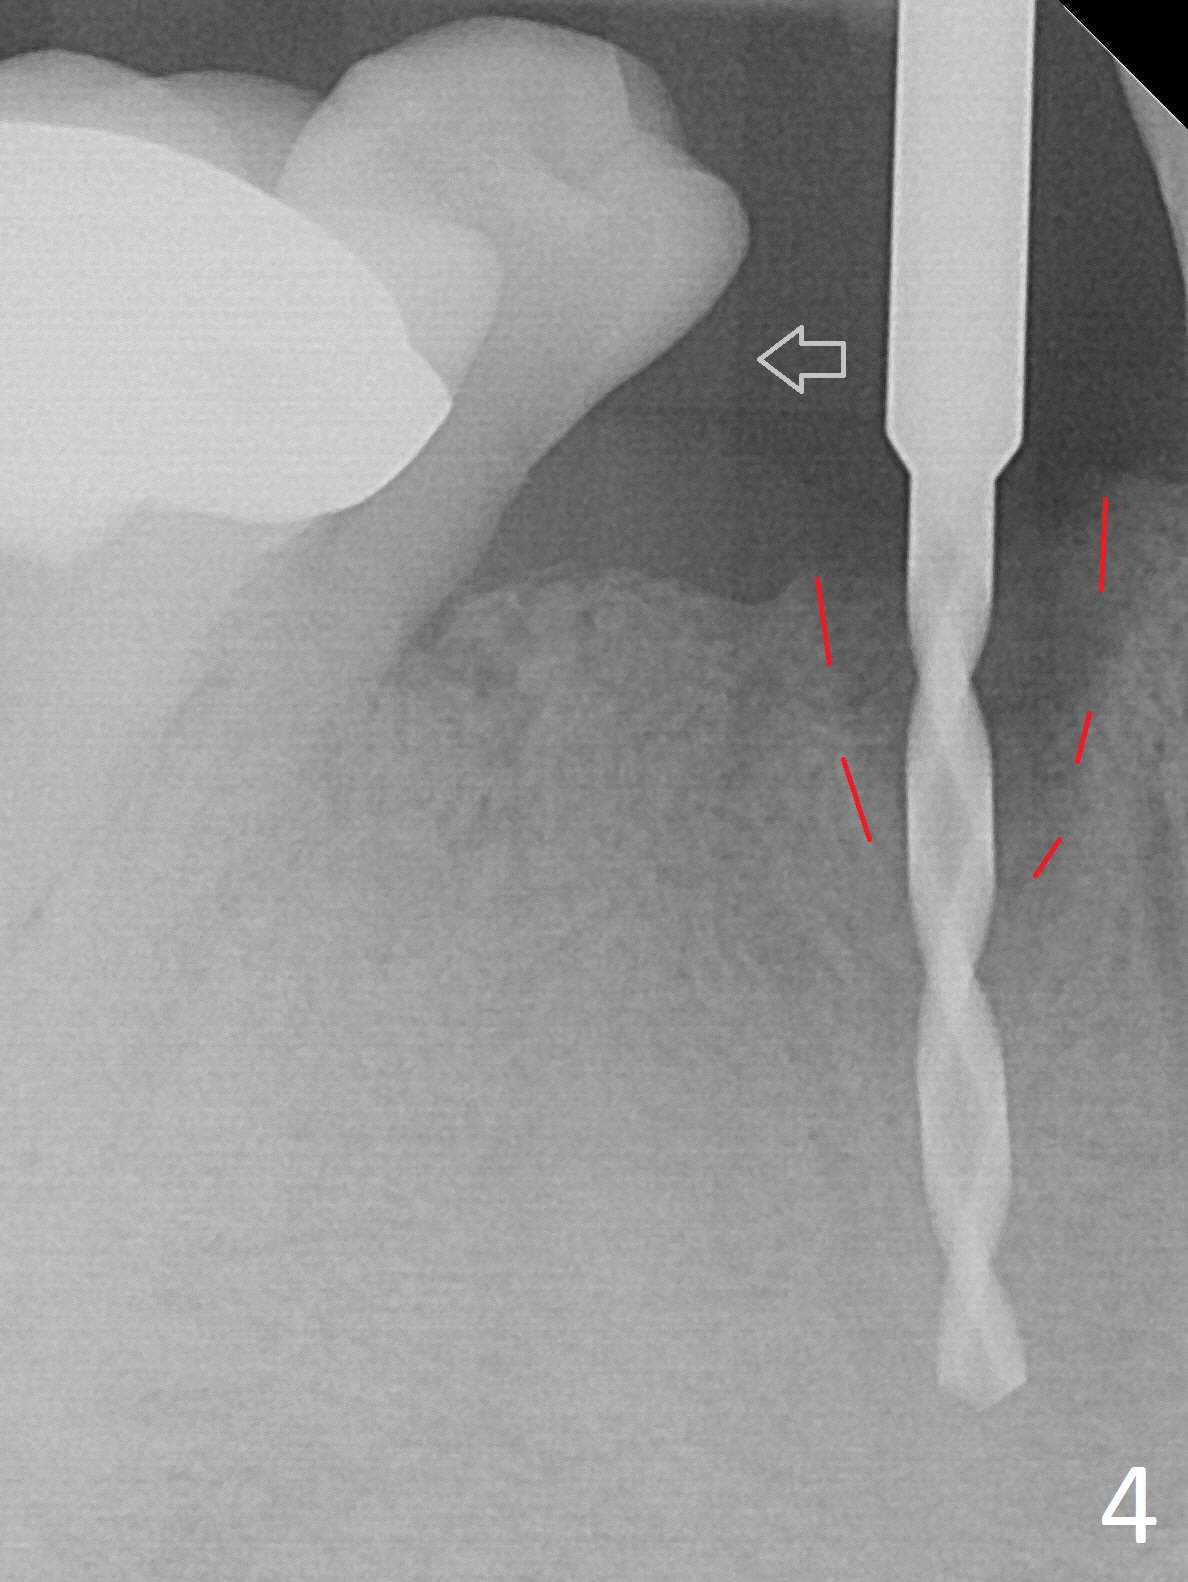

The lower dentition is special, consisting of a residual root (Fig.1 ^), 2 incisor (I), 1 canine (C), 1 premolar (P) and 1 molar (M). The residual root looks like an incisor with rotation of 90º (Fig.2,3). Osteotomy is initiated (Fig.4) for a 3x16(2) mm 1-piece implant (Fig.5 with 45 Ncm). The implant is being placed as distal as possible (Fig.4 arrow) so that a large canine-like provisional is to be fabricated in the large edentulous space (Fig.8,9) after bone graft (Fig.6,7 *). The gingiva around the provisional (Fig.10 P) remains healthy 11 days postop with occlusal clearance against the opposing dentition (Fig.11). The implant threads are not exposed with the help of bone graft 3 months 1 week postop (Fig.12). The gingiva around the implant is healthy (Fig.13). Soft tissue socket is formed by the provisional (Fig.14 *).